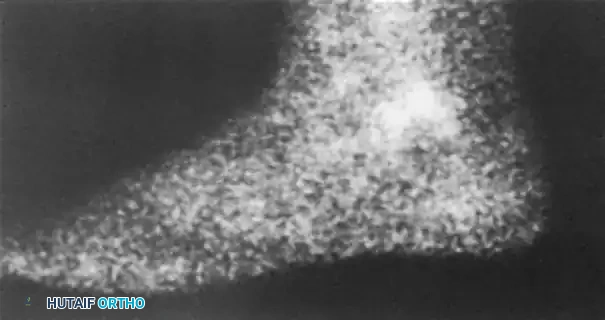

Lateral process fractures of the talus (often termed "snowboarder's fractures") or other talar avulsions can lead to chronic lateral pain and subtalar joint incongruity. Advanced imaging, including bone scans and CT, is highly sensitive for detecting these lesions when plain films are equivocal.

FIGURE 89-35 A: Bone scan demonstrating intense focal uptake in the lateral aspect of the talus, indicative of an occult avulsion fracture.